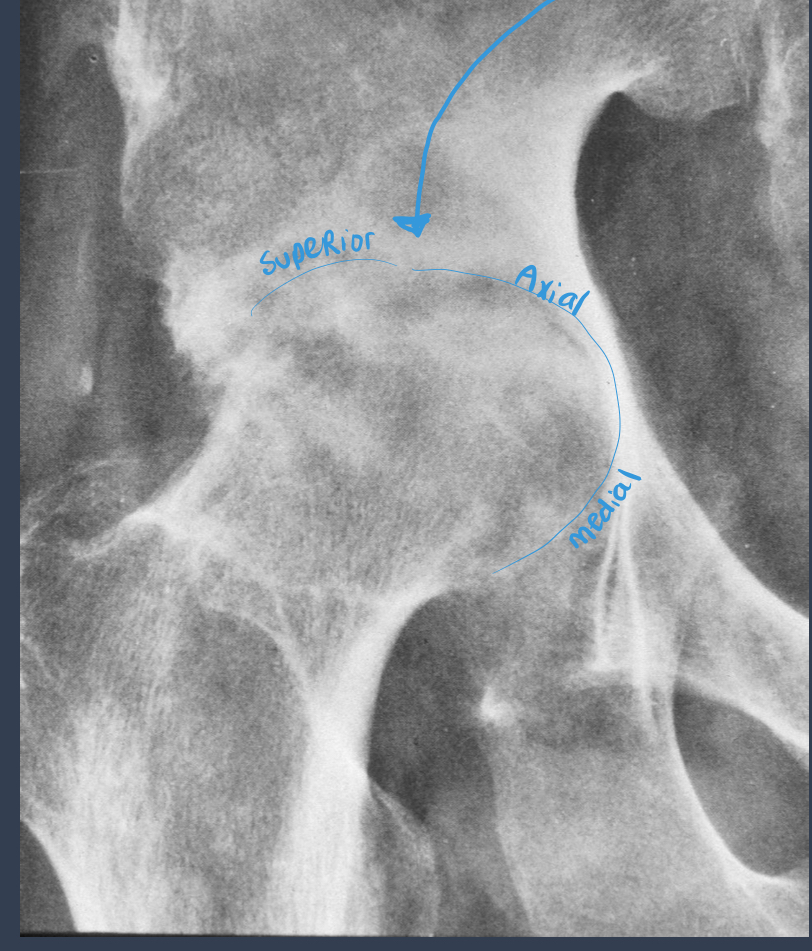

septic arthritis?

what is noted by the arrow here?

loss of joint space

what should be the ratio of the femoral-acetabular joint?

1:1:2

what is this?

septic arthritis

joint space loss

bone destruction

rapid over several weeks